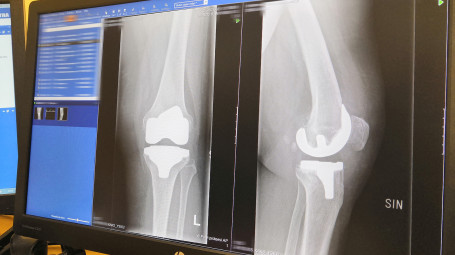

Kainuun keskussairaalassa tehdään röntgen-, magneetti-, mammografia-, luuntiheysmittaus- ja ultraäänitutkimuksia sekä verisuonten tutkimuksia ja pallolaajennuksia.

Röntgentutkimukset, magneettitutkimukset, tietokonetomografiatutkimukset, angiografiatutkimukset, luuntiheysmittaus, mammografiat ja ultraäänitutkimukset